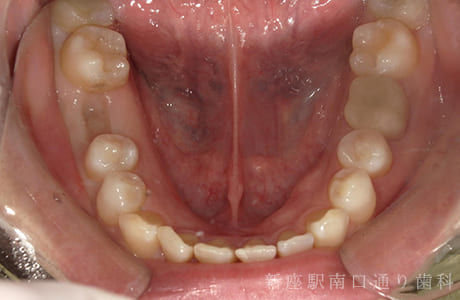

CASE.03

右下6番が破折抜歯後に

フルジルコニアブリッジで修復した症例

- 主訴

- 歯がないところを治したい

- 治療法

- 右下にフルジルコニアブリッジで修復

- 治療期間

- 1ヶ月半

- 費用

- ¥240,000(税込)

右下6番が破折し抜歯後にフルジルコニアブリッジで修復したです。

【リスク・副作用】

過度の咬合や衝撃で割れることがあります。治療直後は歯や歯茎に一時的な違和感や痛みが出ることがあります。